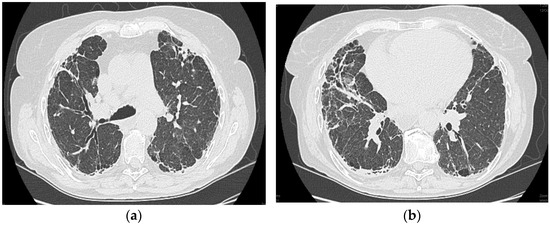

2.1.6. High-Resolution Computed Tomography (12 October 2022) (Figure 2)

Thyroid gland of normal appearance. Advanced fibrotic changes in both lung fields with septal thickening, architectural disorganization, and traction bronchiectasis, with the changes being more important at the basal level of the bilateral lower lobes. Small diffuse calcified granulomas bilaterally, without areas of pulmonary condensation. Absence of suspicious pulmonary nodules. Trachea and bronchi with free lumens. Absence of mediastinal masses. Absence of pleural fluid accumulations. Mediastinal adenopathies up to 17 mm perivascular, 16 mm pretracheal at the right, 18 mm left hilar, 15 mm right hilar, and multiple subcentimeter, some with punctate calcifications. Esophagus minimally dilated with liquid content. Cardiomegaly, pericardial blade up to 18 mm in the right ventricle. Accentuation of dorsal kyphosis. Early degenerative changes in the dorsal spine, without suspicious lesions on the scanned bone segment. Conclusions: Pulmonary fibrosis changes with medium-advanced damage. Pericardial minimum. Esophageal stasis, more likely in the context of achalasia. Bilateral mediastinal and hilar adenopathies, some with calcifications.

2.1.10. High-Resolution Computed Tomography (March First 2023) (Figure 3)

Predominantly subpleural reticular lesions, with a four-cornered appearance, associated with minimal right anterobasal peribronchovascular extension. Traction bronchiectasis is associated with the reticular beaches above. Subpleural areas of honeycombing are more accentuated in the lower half of the lung. Discrete peripheral organizing masses, especially in the left posterior. Fibrous bands with small associated calcifications. The pleural contour is irregularly marked, with numerous spicules on the contour. The esophagus is markedly dilated along its entire length, with a caliber of up to 26 mm, regular walls, and liquid stasis in the lower half. Circumferential pericarditis in a small amount. Global cardiomegaly. The pulmonary artery cone has a caliber of 36 mm, in the context of known pulmonary hypertension. Numerous supracarinal bilateral mediastino-hilar adenopathies, some of them with small calcifications, with an inflammatory appearance. Thyroid with normal position and dimensions, inhomogeneous, micropolynodular structure. Conclusions: The CT appearance is an appearance of interstitial lung pneumopathy: progressive fibrosing phenotype, examination quasi-identical to the previous CT examination. Dilated pulmonary arteries with the appearance of PAH. Minimal pericarditis. Cardiomegaly. Polynodular goiter. Dorsal spondylarthrosis.

Considering the underlying pathology, progressive systemic sclerosis and interstitial lung disease, the next step in the diagnostic process was progressive evaluation. The restrictive pattern expressed on the body plethysmography associated with a significant decrease in DLCO, the clinical deterioration of the patient, and the progression of imaging lesions on HRCT led to the classification of the patient as having an SSC-ILD progressive phenotype.